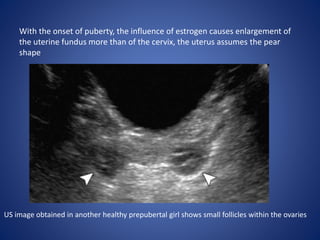

With the onset of puberty, the influence of estrogen causes enlargement of

the uterine fundus more than of the cervix, the uterus assumes the pear

shape

US image obtained in another healthy prepubertal girl shows small follicles within the ovaries